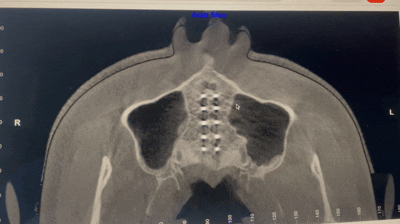

Fme 10mm expansion before after👇👇👇

As you can see there is forward movement.sutures of sphenoid bone and other cranial bones are very much loosened which allows good amount of protraction

As you can see the orbitals everything is moving upward maybe due to more number of tads

Interesting it seeems that face does not get much wider as more movement is in forward direction. Except nose i think looks and health improved of the guy. Eyes seems to change but i need unfeauded pics to see. Eyes are so easy to fraud.

can see the eyes rotating upwards in the cbct